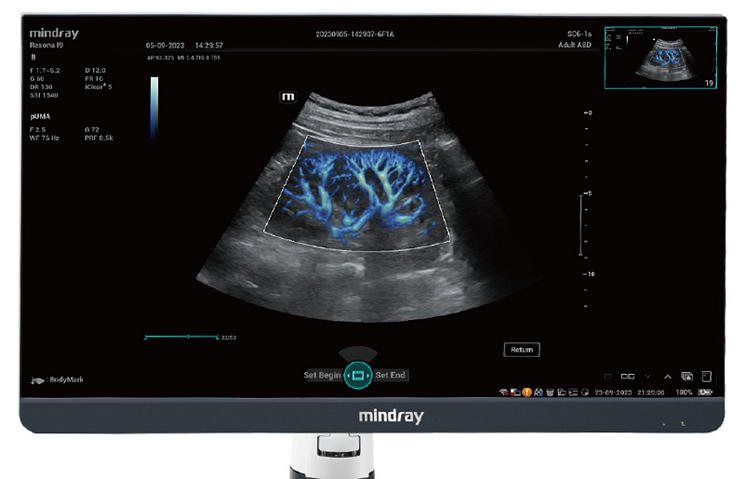

Powered by ZST +

The ZST + platform represents an extraordinary leap forward in ultrasound technology, moving away from traditional beam-forming to channel data processing. This groundbreaking innovation overcomes the traditional trade-offs among spatial resolution, temporal resolution, and tissue uniformity, resulting in unparalleled image quality that empowers infinite imaging solutions.

Resona I9 provides comprehensive clinical solutions for dedicated applications. Based on in-depth insights into different clinical scenarios, it delivers innovations that give users extreme clarity, outstanding intelligence and enhanced diagnostic confidence.